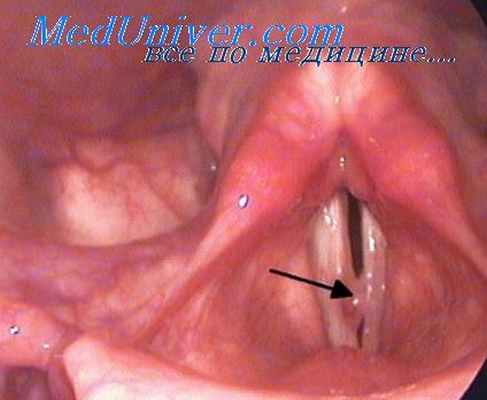

Наиболее простым и доступным методом исследования дыхательной и речевой функции является ларингоскопия. Акт фонации при этом исследовании обнаруживает состояние голоса, а ларингоскопическая картина показывает амплитуду движения голосовых связок кнутри, к средней линии.

В момент дыхания изображение в зеркале показывает размеры гортанной щели и просвета видимой части трахеи, проходимость этих путей для воздуха, а также амплитуду движения голосовых связок кнаружи.

Для более детального и тщательного исследования голосовой функции примепяют стробоскопию.

Ларингостробоскопия (по-гречески strobos—кружение, scoрео — смотрю) является методом исследования быстрых движений (вибраций) голосовых связок. При обычной ларингоскопии (зеркальной и прямой) голосовые связки в момент фонации (когда исследуемый тянет звук «э» или «и») кажутся неподвижными. Между тем известно, что они при этом, как всякое звучащее тело, вибрируют. Объясняется эта иллю зия тем, что наш глаз воспринимает колебания частотой только до 16 раз в секунду. Число же колебании голосовых связок даже при наиболее низких (басовых) нотах - не менее 32. Быстро сменяющиеся зрительные раздражения, исходящие от вибрирующей связки, наслаиваются одно на другое, вызываемые ими зрительные ощущении сливаются, и создается впечатление неподвижности связки.

При использовании ларингоскопии (прямой и непрямой) в момент фонации голосовые складки кажутся статичными, но при этом они вибрируют с частотой от 50 до 1024 Гц. Это иллюзия объясняется тем, что наш глаз воспринимает колебания частотой только до 16 раз в секунду, т.е. превосходит физиологические возможности нашего органа зрения. Создается впечатление неподвижности голосовой складки за счет того, что быстро сменяющиеся зрительные раздражения, исходящие от вибрирующей складки, наслаиваются одно на другое.

Принцип действия стробоскопа состоит в оптической иллюзии, при которой частота вспышек света совпадает с частотой колебаний голосовых складок. Возможность подробно рассмотреть вибрационные свойства голосовых складок в фазах открытия и закрытия голосовой щели возникает при несовпадении колебаний складок и вспышек света, при которых будут фиксироваться медленные движения слизистой оболочки голосовых складок.

При обычной ларингоскопии голосовые складки во время фонации находятся в положении аддукции (приведение к средней линии) и выглядят неподвижными, тогда как в действительности они совершают быстрые движения, сближая и удаляя свои края с максимальной амплитудой в средней части. Глаз человека без специального прибора уловить эти колебания не может, так как фонаторные колебания голосовых складок имеют частоту, намного превышающую предел возможности зрительного анализатора. Чтобы это стало возможным, в ларингологии и фониатрии применен стробоскопический принцип.

При ларингостробоскопии для освещения применяется лампа с короткими световыми импульсами. Свет от импульсного освещения, как и при обычной ларингоскопии, направляется от лобного рефлектора на гортанное зеркало и далее в гортань. При освещении голосовых складок прерывистым светом, синхронным с частотой колебаний, можно наблюдать их в определённые фазы колебания, при этом голосовые складки будут казаться неподвижными. При нарушении синхронности между частотой вспышек импульсной лампы и частотой колебаний голосовых складок создается впечатление. Что они колеблются медленно. Это кажущееся движение – верное отображение действительных колебаний.

У здоровых лиц ларингостробоскопическая картина имеет характерные признаки. В картине «движения» у них всегда наблюдаются типичные противоположные по направлению друг к другу колебания всей массы голосовых складок, преимущественно в горизонтальной плоскости. Колебания, как правило, носят равномерный характер как по амплитуде, так и по частоте. Во время приведения голосовых складок к средней линии отмечается смыкание их внутреннего края по всей длине. Смещение слизистой оболочки по свободному краю голосовых складок отчетливо наблюдается в 75-80% случаев. В картине «остановки» голосовые складки выглядят неподвижными и занимают в зависимости от фазы фиксации положение от срединного до бокового. Увеличение амплитуды колеблющихся голосовых складок может наблюдаться при усилении интенсивности звучания голоса, а уменьшение – при повышении частоты тона благодаря изменению напряжения голосовых складок.